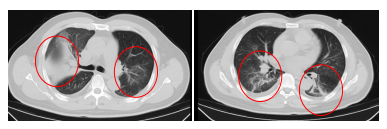

發熱門診醫生詳細詢問顧先生的既往病史,併為其進行細緻的體格檢查。胸部CT結果顯示, 顧先生的雙肺存在大面積的炎症病變**。**

鑑於顧先生的肺部感染情況較為嚴重,門診醫生立即將其收住感染科病房接受進一步治療